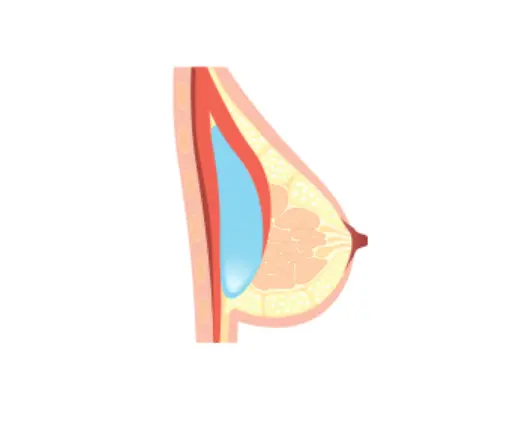

Implant Placement Options

| Placement | Above Muscle | Under Muscle | Dual Plane (Partial Submuscular) |

|---|---|---|---|

| Advantages | – Suitable for sagging or deflated breasts – Natural shape – Less pain and simpler surgery | – Suitable for smaller breasts – Can prevent capsular contracture – More natural result | – For patients with thin skin or low body fat – Reduces implant visibility – Prevents infection – Keeps implant securely in place |

| Disadvantages | – May look unnatural if patient has little fat – Higher risk of capsular contracture | – Slight pain due to tension between muscle and implant – Slightly longer recovery time | – Difficult to position implant if muscles are thick – Risk of muscle tearing or asymmetry |

Above Muscle

Under Muscle

Dual Plane (Partial Submuscular)